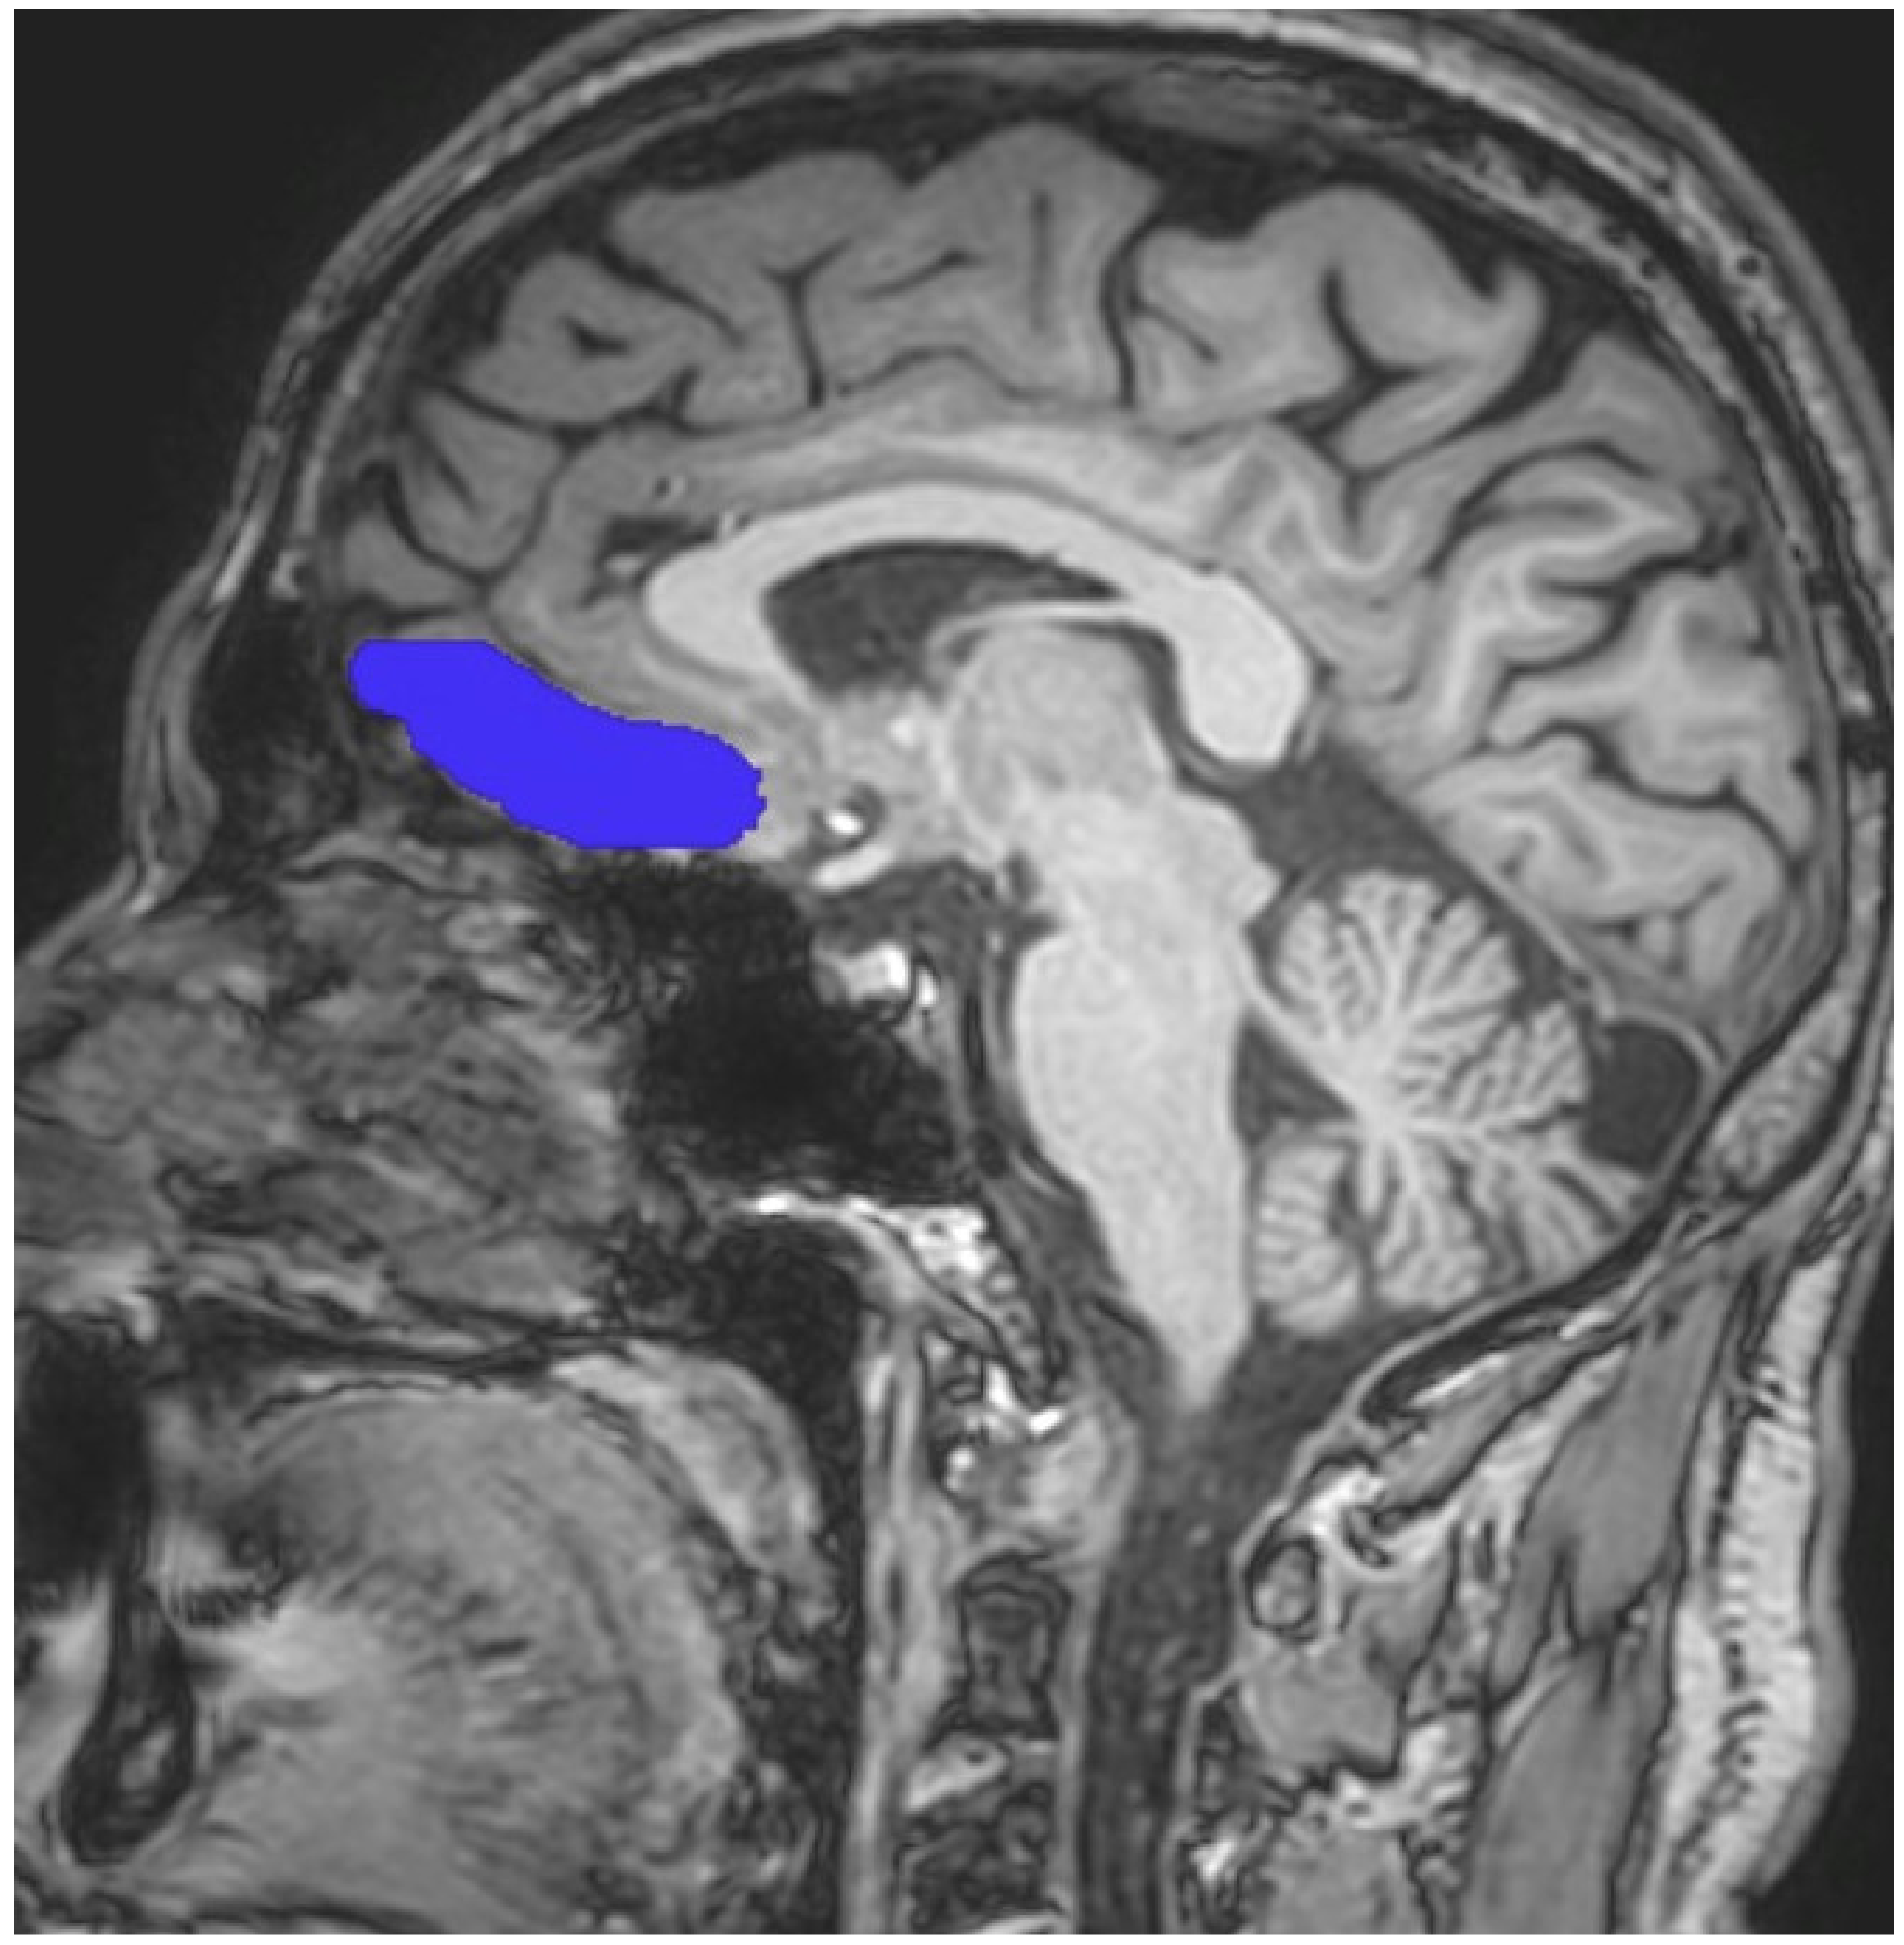

Image analyses were carried out using the FreeSurfer program (version 4.4), a free program to use and available to download online, which was used to reconstruct the cortical surfaces and detect the cortical thickness from magnetic resonance images (http://surfer.nmr.mgh.harvard.edu, accessed on 10 November 2022). For all processes, the method of Epstein et al. was followed [39]. The process utilised to analyse each subject’s brain images is available on the FreeSurfer website. Scans were processed by a radiologist who was blind to both the diagnosis of patients with alcohol use disorder and to whom was a patient or a healthy control subject. The process included motion correction, extraction of the brain tissue, transformation to Talairach space, segmentation and parcellation into the OFC region as described by Desikan et al. [40]. After this process, scans were also examined by a senior radiologist (M.K.) to ensure that segmentation and parcellation were performed correctly. In addition, scans were also reviewed for the presence of any artifact. However, no artifact was found. Uncorrected OFC cortical volumes (mm3) were divided by the total segmented brain volume (mm3) and then multiplied by 1000, to obtain the corrected cortical volumes. In contrast to Epstein et al.’s study, the OFC region was investigated in two parts, as left and right OFC [39]. Assistance was obtained from standard neuroanatomy atlases during all measurements [41,42,43]. On the other hand, the boundaries of the OFC region were adapted from Portas et al. and Riffkin et al. [44,45]. By using those guidelines, the same procedure as in our previous studies was preferred [46,47]. When determining the volumes of the OFC, the superior boundary of the OFC was defined by a line extending from the anterior commissure to the posterior commissure. The point at which the olfactory sulcus first appeared was determined as the posterior landmark. As expected, while the inferior boundary of the OFC was selected the most inferior aspect of the cortex, the most lateral edge of the brain cortex was also accepted as the lateral boundary of OFC. Finally, the longitudinal fissure was accepted as the medial boundary of the OFC. Sample imaging owing to the OFC is presented in Figure 1, whereas the images obtaining from the Freesurfer program are presented in Figure 2.

Figure 1.

Sample manual tracing for the OFC.